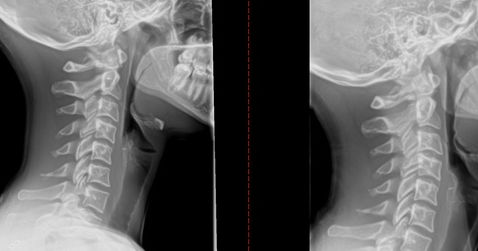

Often patients suffer from a loss of a cervical lordosis. Your neck is meant to have a curve, this curve gives your neck and spine give. When you lose this natural curve we get headaches and other issues.  If not addressed this loss of lordosis can lead to degenerative disc disease and neuropathy. At Moreland Chiropractic Clinic will utilize a McKenzie method to help restore this normal lordotic curve and ease your headaches. The process is simple and involves the patient in care as well. We asked the patient to do home therapy and exercises as well as use ice. We utilize specific chiropractic manipulations that gently help restore the curve. Check out our reviews. We would love the opportunity to help you.